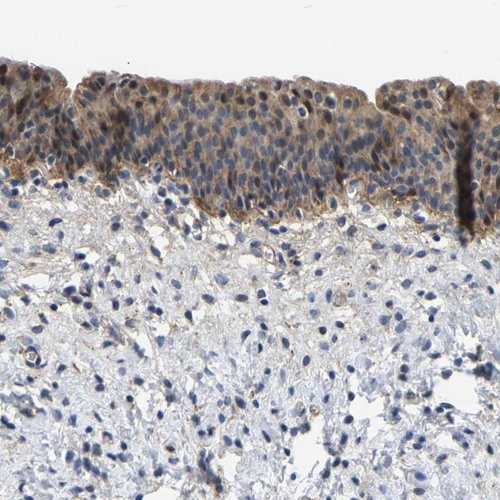

Immunohistochemical staining of human urinary bladder shows moderate positivity in urothelial cells.